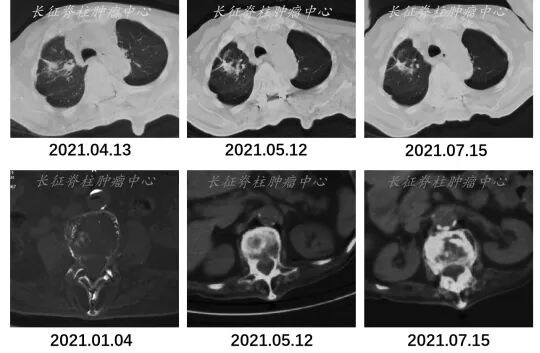

X线:因疼痛导致的脊柱侧弯、因椎体压缩导致的脊柱后突畸形。

图1. X线检查结果

MRI:胸5-9椎体信号异常,T7椎体压缩骨折,T4-8椎管内占位。

图2. MRI检查结果